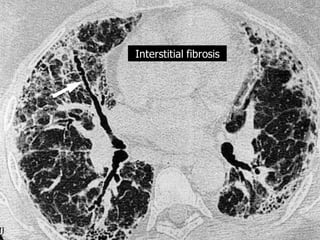

Idiopathic pulmonary fibrosis

Interstitial fibrosis

Honeycombing

F 78Y Diabetic and hypertensive presented with severe dyspnea

suspected to pulmonary embolism , treated with anticoagulants with mild

improvement